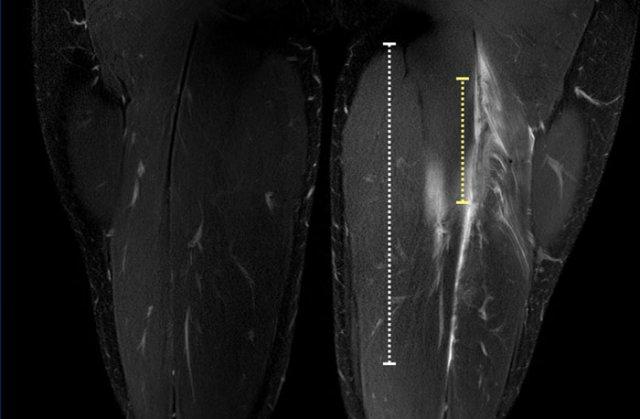

Video về tổn thương gân cơ hamstring bán phần. Lưu ý chiều dài vùng phù nề cơ và chiều dài đoạn gân biến dạng. Do cả hai đặc điểm này đều trải dài trên một khoảng cách đáng kể, đây là các yếu tố tiên lượng xấu.

Tại đây bạn có thể cuộn qua các hình ảnh axial. Có thể phóng to hình ảnh bằng cách nhấp vào chúng.

Đây là tổn thương bán phần, bắt đầu từ gân chung ở phía gần, bao gồm cả vùng MTJ và gân trong cơ ở phía xa hơn. Chiều dài vùng phù nề và mức độ biến dạng gân đều ở mức độ cao. Trường hợp này được phân loại là tổn thương BAMIC 3b/c.